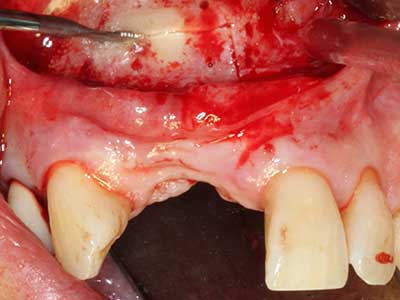

Fig. 13: Adequate irrigation with the 4-mm residual bone width is essential for this 52-year-old patient during the bone splitting.

Fig. 14: Placement of four tapered RSX implants (Bego Implant Systems, Bremen).